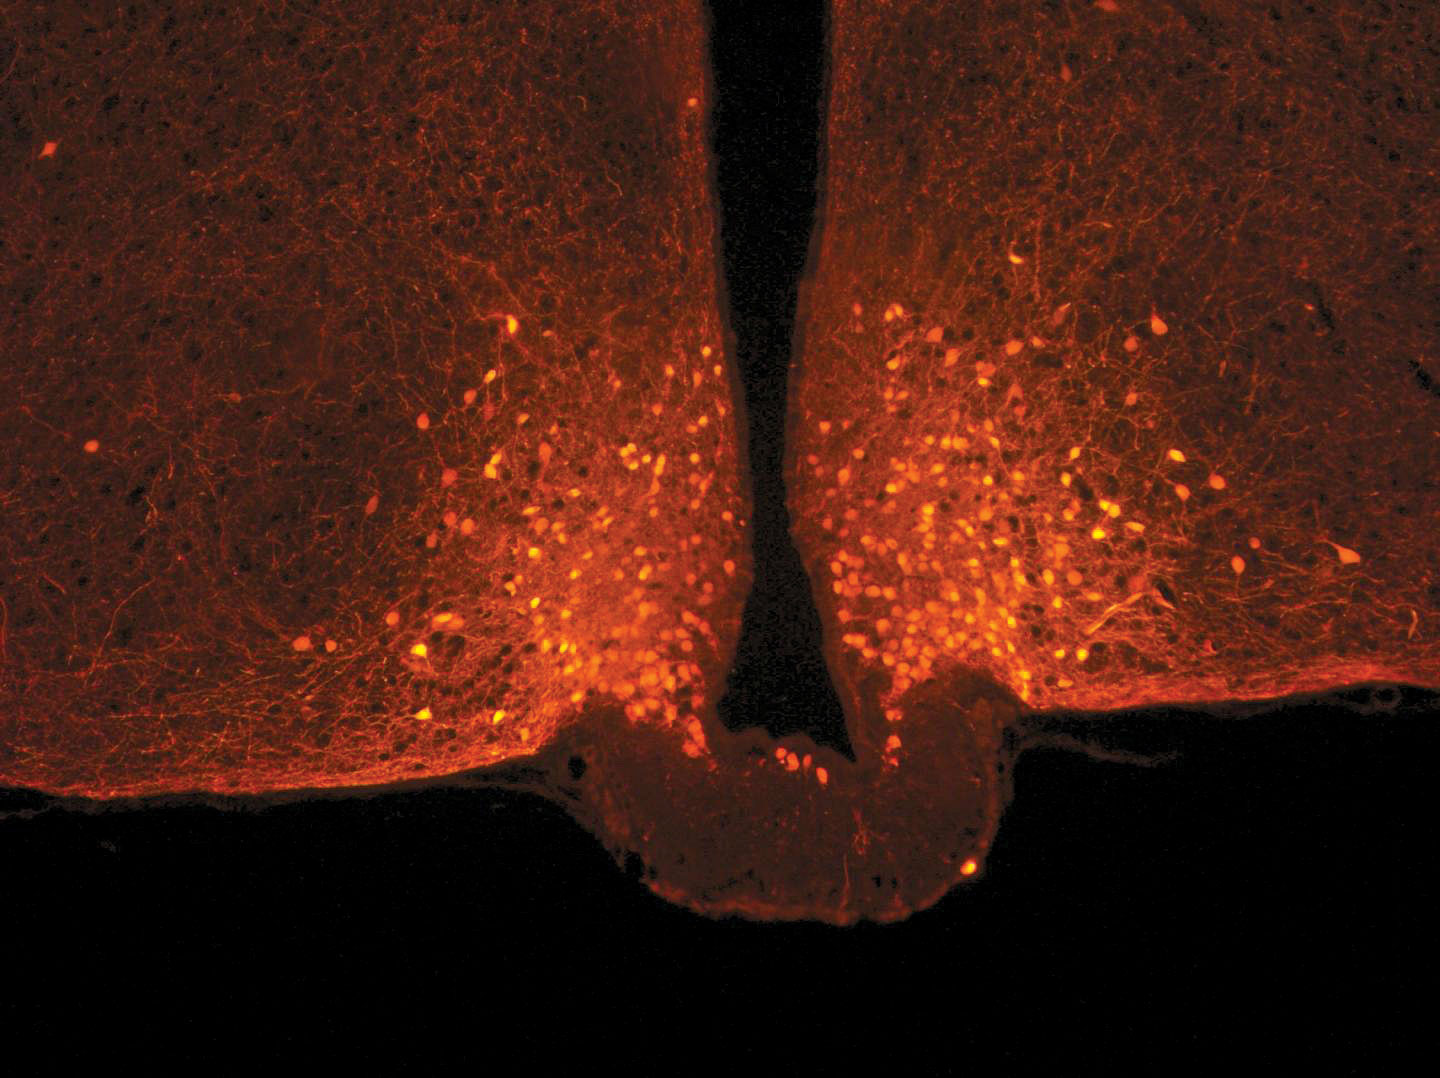

ركَّز العلماء على الخلايا العصبية في سلسلة الأحماض الأمينية التي تسمى (POMC) في منطقة ما تحت المهاد (hypothalamus)، الموجودة في قاعدة الدماغ السفلية، والمعروفة بوظيفة الحد من تناول الطعام. والتي ترتبط أيضاً بعدد كبير من الخلايا العصبية في أجزاء أخرى من الدماغ بواسطة روابط هذه الدائرة القابلة للتغير، إذ يمكن تشغيلها وإيقافها بسرعة كبيرة بناءً على التقلبات الهرمونية. ولاحظ الباحثون أن هذه الدائرة العصبية لا يتم تعديلها بعد تناول وجبة متوازنة، ولكن الخلايا العصبية الأخرى المرتبطة بالخلايا العصبية (POMC)، والمعروفة باسم الخلايا النجمية، هي ما يتغير شكلها.

هذه الخلايا التي هي على شكل نجمة تمَّت دراستها هنا لأول مرَّة من أجل دورها في ما يتعلق بالخلايا العصبية: ففي ظل الظروف المعتادة، تتصرف هذه الخلايا النجمية مثل “فرامل”، وتحد من نشاط خلايا (POMC) العصبية. وبعد تناول الوجبة، تزداد مستويات الجلوكوز في الدم (الجلوكيميا) مؤقتاً، حيث تكتشف الخلايا النجمية هذه الإشارة وتنكمش: بمجرد تشغيل هذا “الفرامل”، يتـم تنشيط الخلايا العصبية (POMC)، مما يعزّز الشعور بالشبع.

Danaé Nuzzaci / CNRS / CSGA ©